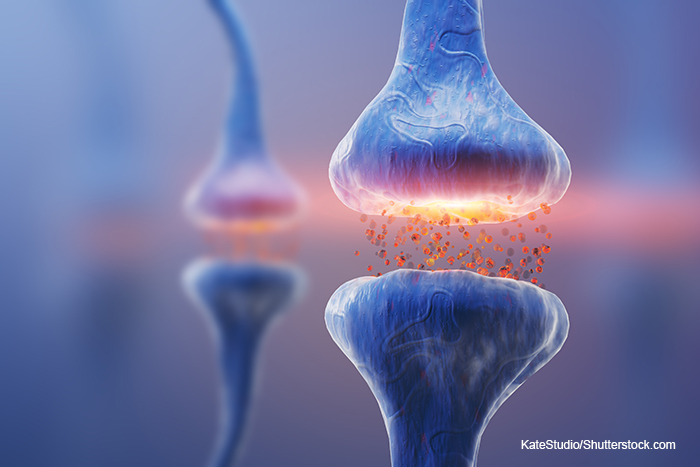

Working in a mouse model, Liu and her research team found that a single stressful event produced quick and long-lasting changes in astrocytes, the brain cells that clean up chemical messengers called neurotransmitters after they’ve communicated information between nerve cells. The stressful episode caused the branches of the astrocytes to shrink away from the synapses, the spaces across which information is transmitted from one cell to another.

The team also discovered a mechanism resulting in communication disruption. They found that during a stressful event, the stress hormone norepinephrine suppresses a molecular pathway that normally produces a protein, GluA1, without which nerve cells and astrocytes cannot communicate with each other.“Stress affects the structure and function of both neurons and astrocytes,” notes Dr. Liu. “Because astrocytes can directly modulate synaptic transmission and are critically involved in stress-related behavior, preventing or reversing the stress-induced change in astrocytes is a potential way to treat stress-related neurological disorders. We identified a molecular pathway that controls GluA1 synthesis and thereby astrocyte remodeling during stress. This suggests new pharmacological targets for possible prevention or reversal of stress-induced changes.”